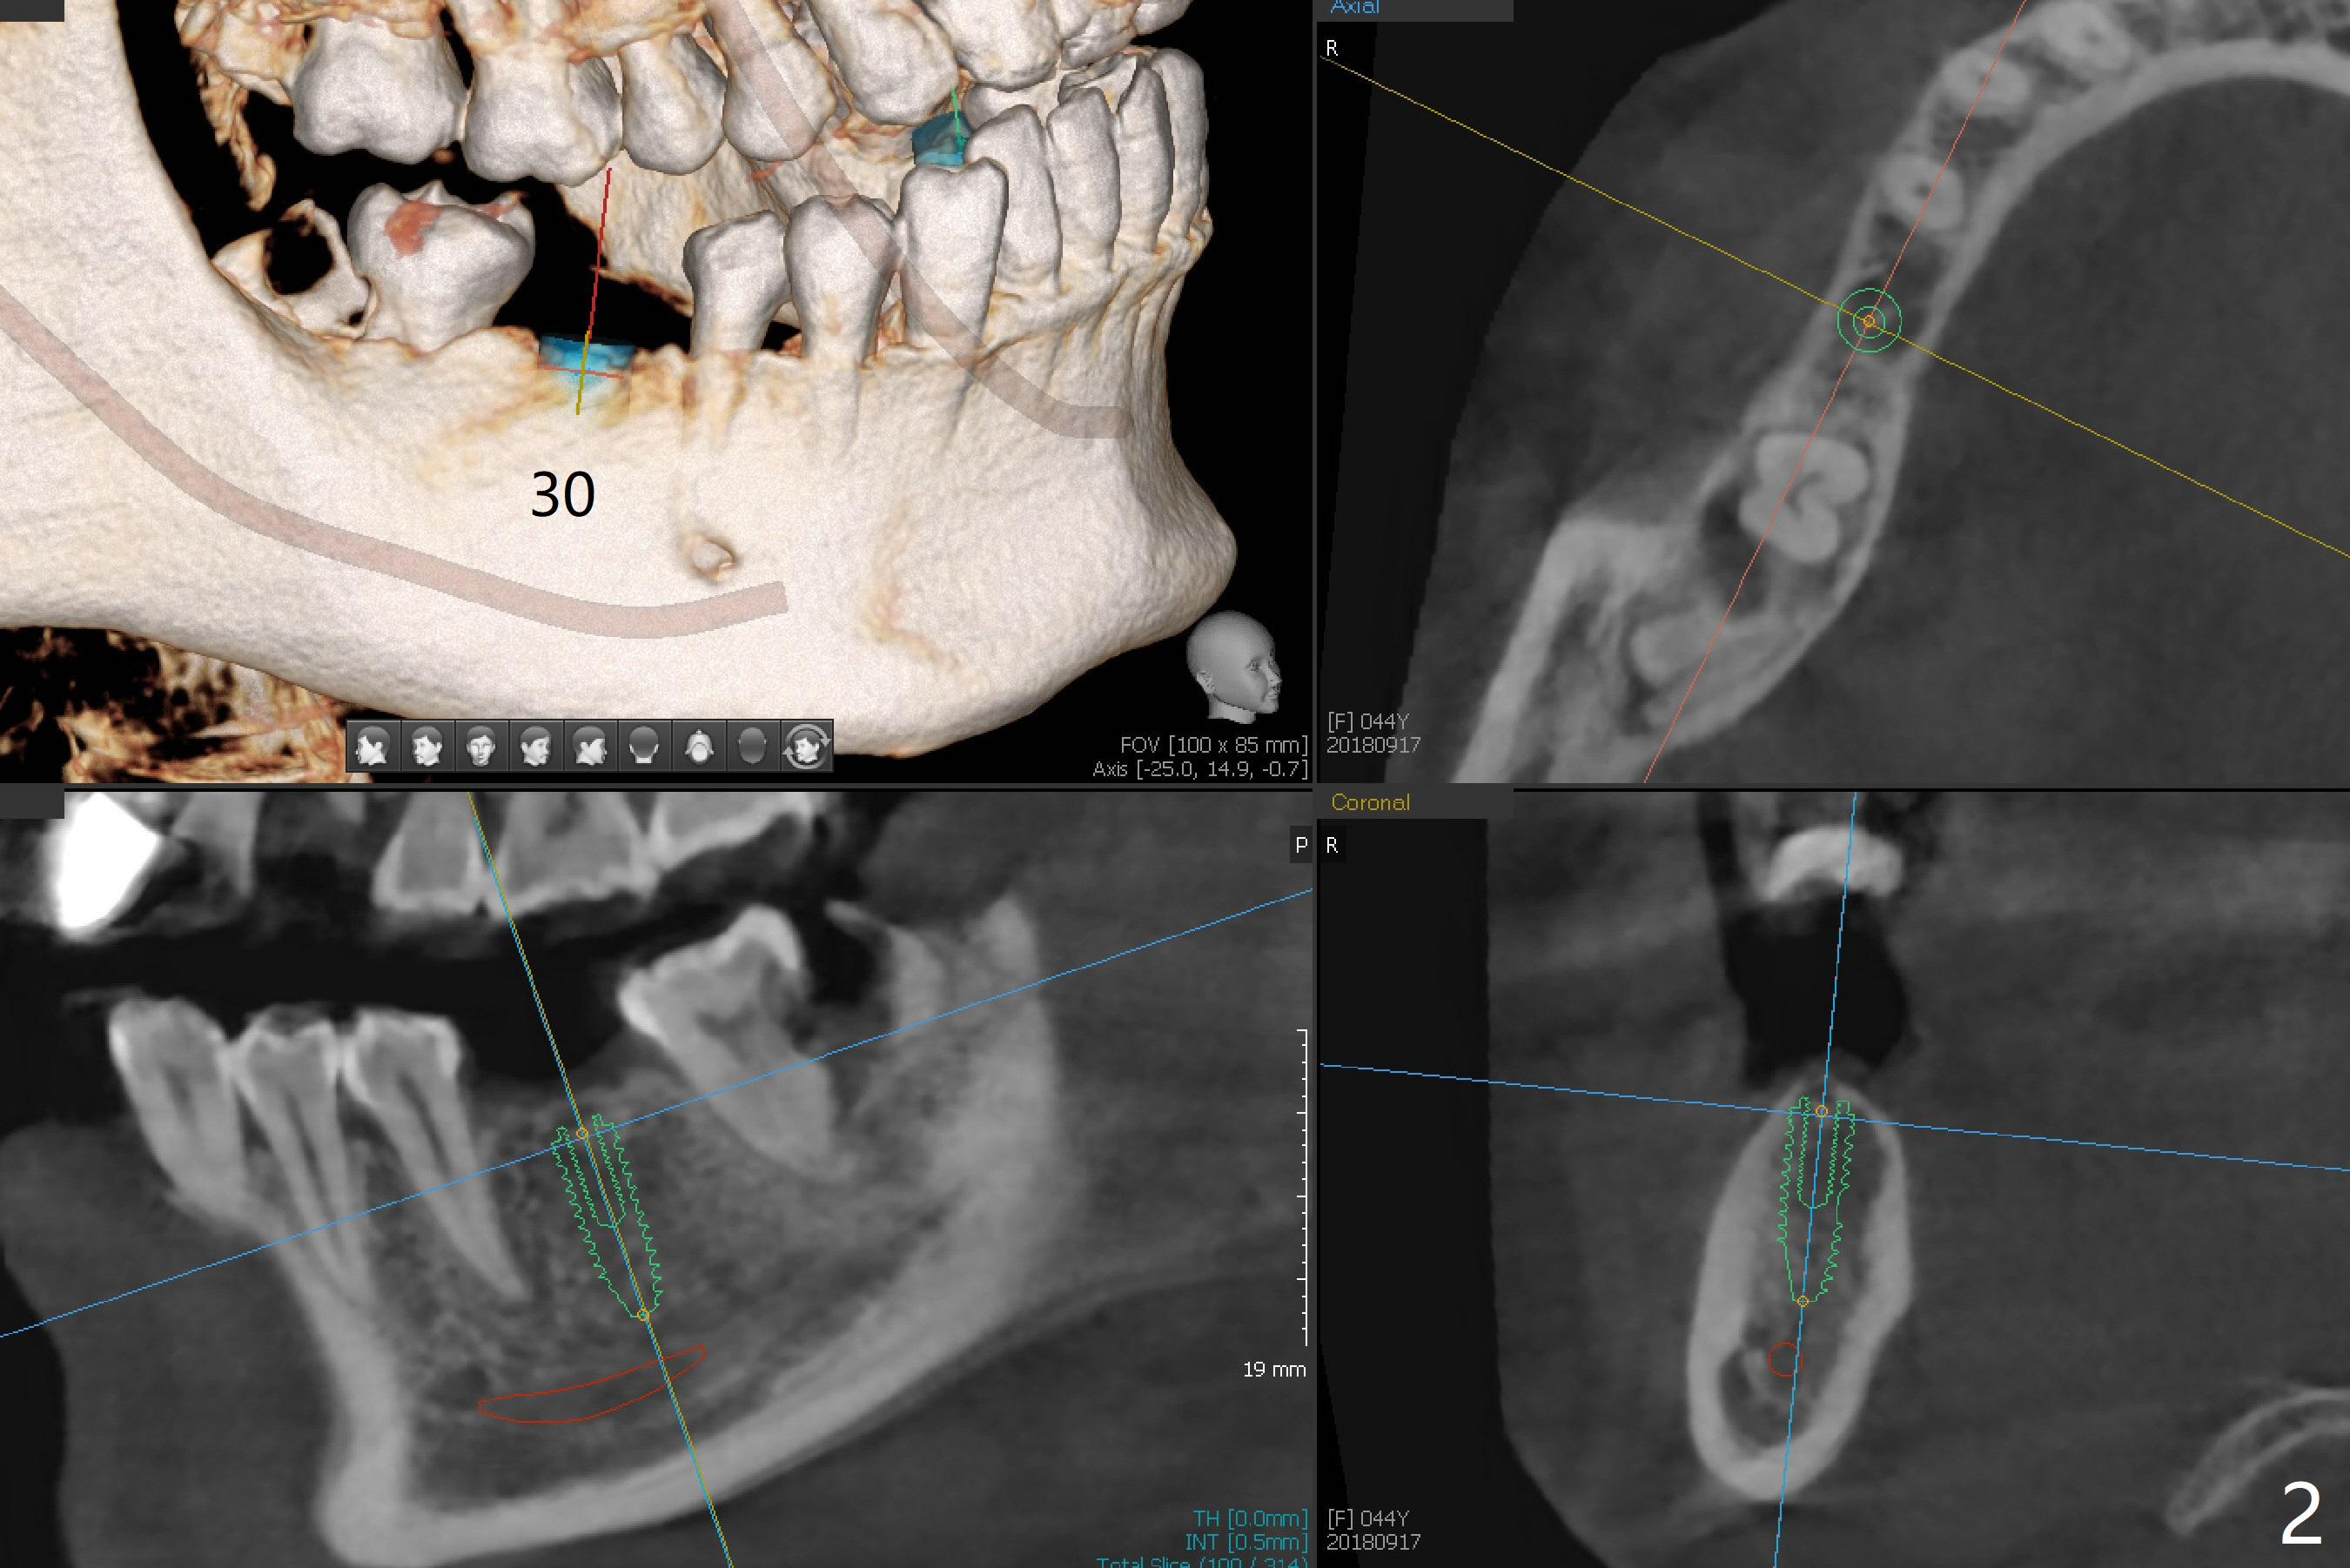

A 44-year-old woman is extremely nervous about dentistry. She presents to office with #15 infection (Fig.1). Since there is malocclusion on the left side (#13 cross bite, 14,18 supraeruption, and 17 and 18 mesial tilt) and she refuses orthodontic treatment, the tooth #15 will be extracted without implant before she leaves for China in 4 months. Guided implant at #30 will be placed first to show that the procedure is painless (Fig.2). In fact an appointment is made for #32 extraction and #31 composite or sedative filling, but she is reluctant to have them done.